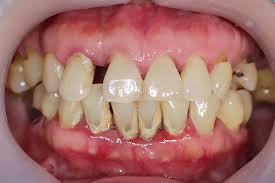

Periodontitis

results in progressive irreversible destruction of the periodontal ligament and supporting alveolar bone

JE on cementum; >4mm of pocket depth

characterization: apical migration of JE, loss of connective tissue attachment, and loss of alveolar bone

marginal gingivitis vs diffuse gingivitis

marginal gingivitis → affect gingival margin and papilla

diffuse gingivitis → extend to include the gingival margin, papilla, and attached gingiva